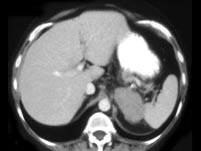

问题 女,47岁,满月脸、向心性肥胖伴高血压1月,请结合所提供图像,作出诊断 ( )

选项 A、左肾上腺嗜铬细胞瘤 B、左肾上腺增生 C、左肾上腺腺癌 D、左肾上腺转移瘤 E、左肾上腺腺瘤

答案 C